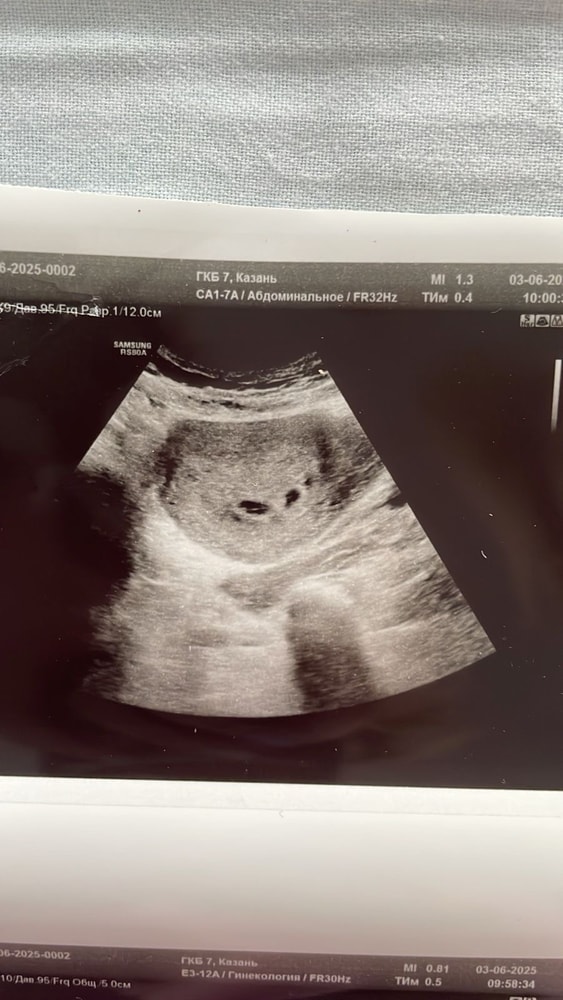

Девочки,это двойня?

Срок маленький,эмбрионсиклв еще не видно,поэтому пока врач ставит под вопросом 🙏🏻 из вашего опыта,что скажите? Срок 5-6 недель